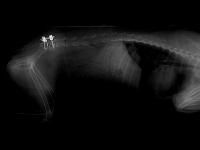

Karen M. Vernau, DVM, MAS, DACVIM (Neurology), of UC Davis Neurology/Neurosurgery Service, worked with the Anesthesia and Diagnostic Imaging Services to perform an MRI on Flynn to see the full extent of the his injuries. The MRI showed the UC Davis team that he suffered from a fracture of his L7 vertebra, and a lumbosacral luxation was compressing the nerves, causing him to have intense pain in his back legs and pelvis. Flynn was then taken for a CT scan to help the team determine next steps to repair the damage to his vertebra.1

Flynn then received a dorsal laminectomy to help relieve the pressure on his spinal nerve, and his L7 fracture was stabilized with a specialized metal implant. He spent 6 days in the hospital and slowly began to improve his pelvic limb motor function and his comfort level. Flynn was able to leave the hospital without any apparent pain, and one of the veterinary technicians at the hospital agreed to foster him.